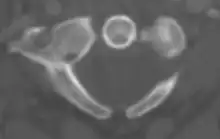

The atlas's chief peculiarity is that it has no body,[3] which has fused with the next vertebra.[4] It is ring-like and consists of an anterior and a posterior arch and two lateral masses.

Anterior arch

The anterior arch forms about one-fifth of the ring: its anterior surface is convex, and presents at its center the anterior tubercle for the attachment of the Longus colli muscles and the anterior longitudinal ligament; posteriorly it is concave, and marked by a smooth, oval or circular facet (fovea dentis), for articulation with the odontoid process (dens) of the axis.

The upper and lower borders respectively give attachment to the anterior atlantooccipital membrane and the anterior atlantoaxial ligament; the former connects it with the occipital bone above, and the latter with the axis below.[5]

Posterior arch

The posterior arch forms about two-fifths of the circumference of the ring: it ends behind in the posterior tubercle, which is the rudiment of a spinous process and gives origin to the Recti capitis posteriores minores and the ligamentum nuchae. The diminutive size of this process prevents any interference with the movements between the atlas and the skull.

The posterior part of the arch presents above and behind a rounded edge for the attachment of the posterior atlantooccipital membrane, while immediately behind each superior articular process is the superior vertebral notch (sulcus arteriae vertebralis). This is a groove that is sometimes converted into a foramen by ossification of the posterior atlantooccipital membrane to create a delicate bony spiculum which arches backward from the posterior end of the superior articular process. This anatomical variant is known as an arcuate foramen.

This groove transmits the vertebral artery, which, after ascending through the foramen in the transverse process, winds around the lateral mass in a direction backward and medially to enter the vertebrobasilar circulation through the foramen magnum; it also transmits the suboccipital nerve (first spinal nerve)

On the under surface of the posterior arch, behind the inferior articular facets, are two shallow grooves, the inferior vertebral notches. The lower border gives attachment to the posterior atlantoaxial ligament, which connects it with the axis.

Lateral masses

The lateral masses are the most bulky and solid parts of the atlas, in order to support the weight of the head.

Each carries two articular facets, a superior and an inferior.

- The superior facets are of large size, oval, concave, and approach each other in front, but diverge behind: they are directed upward, medially, and a little backward, each forming a cup for the corresponding condyle of the occipital bone, and are admirably adapted to the nodding movements of the head. Not infrequently they are partially subdivided by indentations which encroach upon their margins.

- The inferior articular facets are circular in form, flattened or slightly convex and directed downward and medially, articulating with the axis, and permitting the rotatory movements of the head.

Vertebral foramen

Just below the medial margin of each superior facet is a small tubercle, for the attachment of the transverse atlantal ligament which stretches across the ring of the atlas and divides the vertebral foramen into two unequal parts:

- the anterior or smaller receiving the odontoid process of the axis

- the posterior transmitting the spinal cord (medulla spinalis) and its membranes

This part of the vertebral canal is of considerable size, much greater than is required for the accommodation of the spinal cord.

Transverse processes

The transverse processes are large; they project laterally and downward from the lateral masses, and serve for the attachment of muscles which assist in rotating the head. They are long, and their anterior and posterior tubercles are fused into one mass; the foramen transversarium is directed from below, upward and backward.